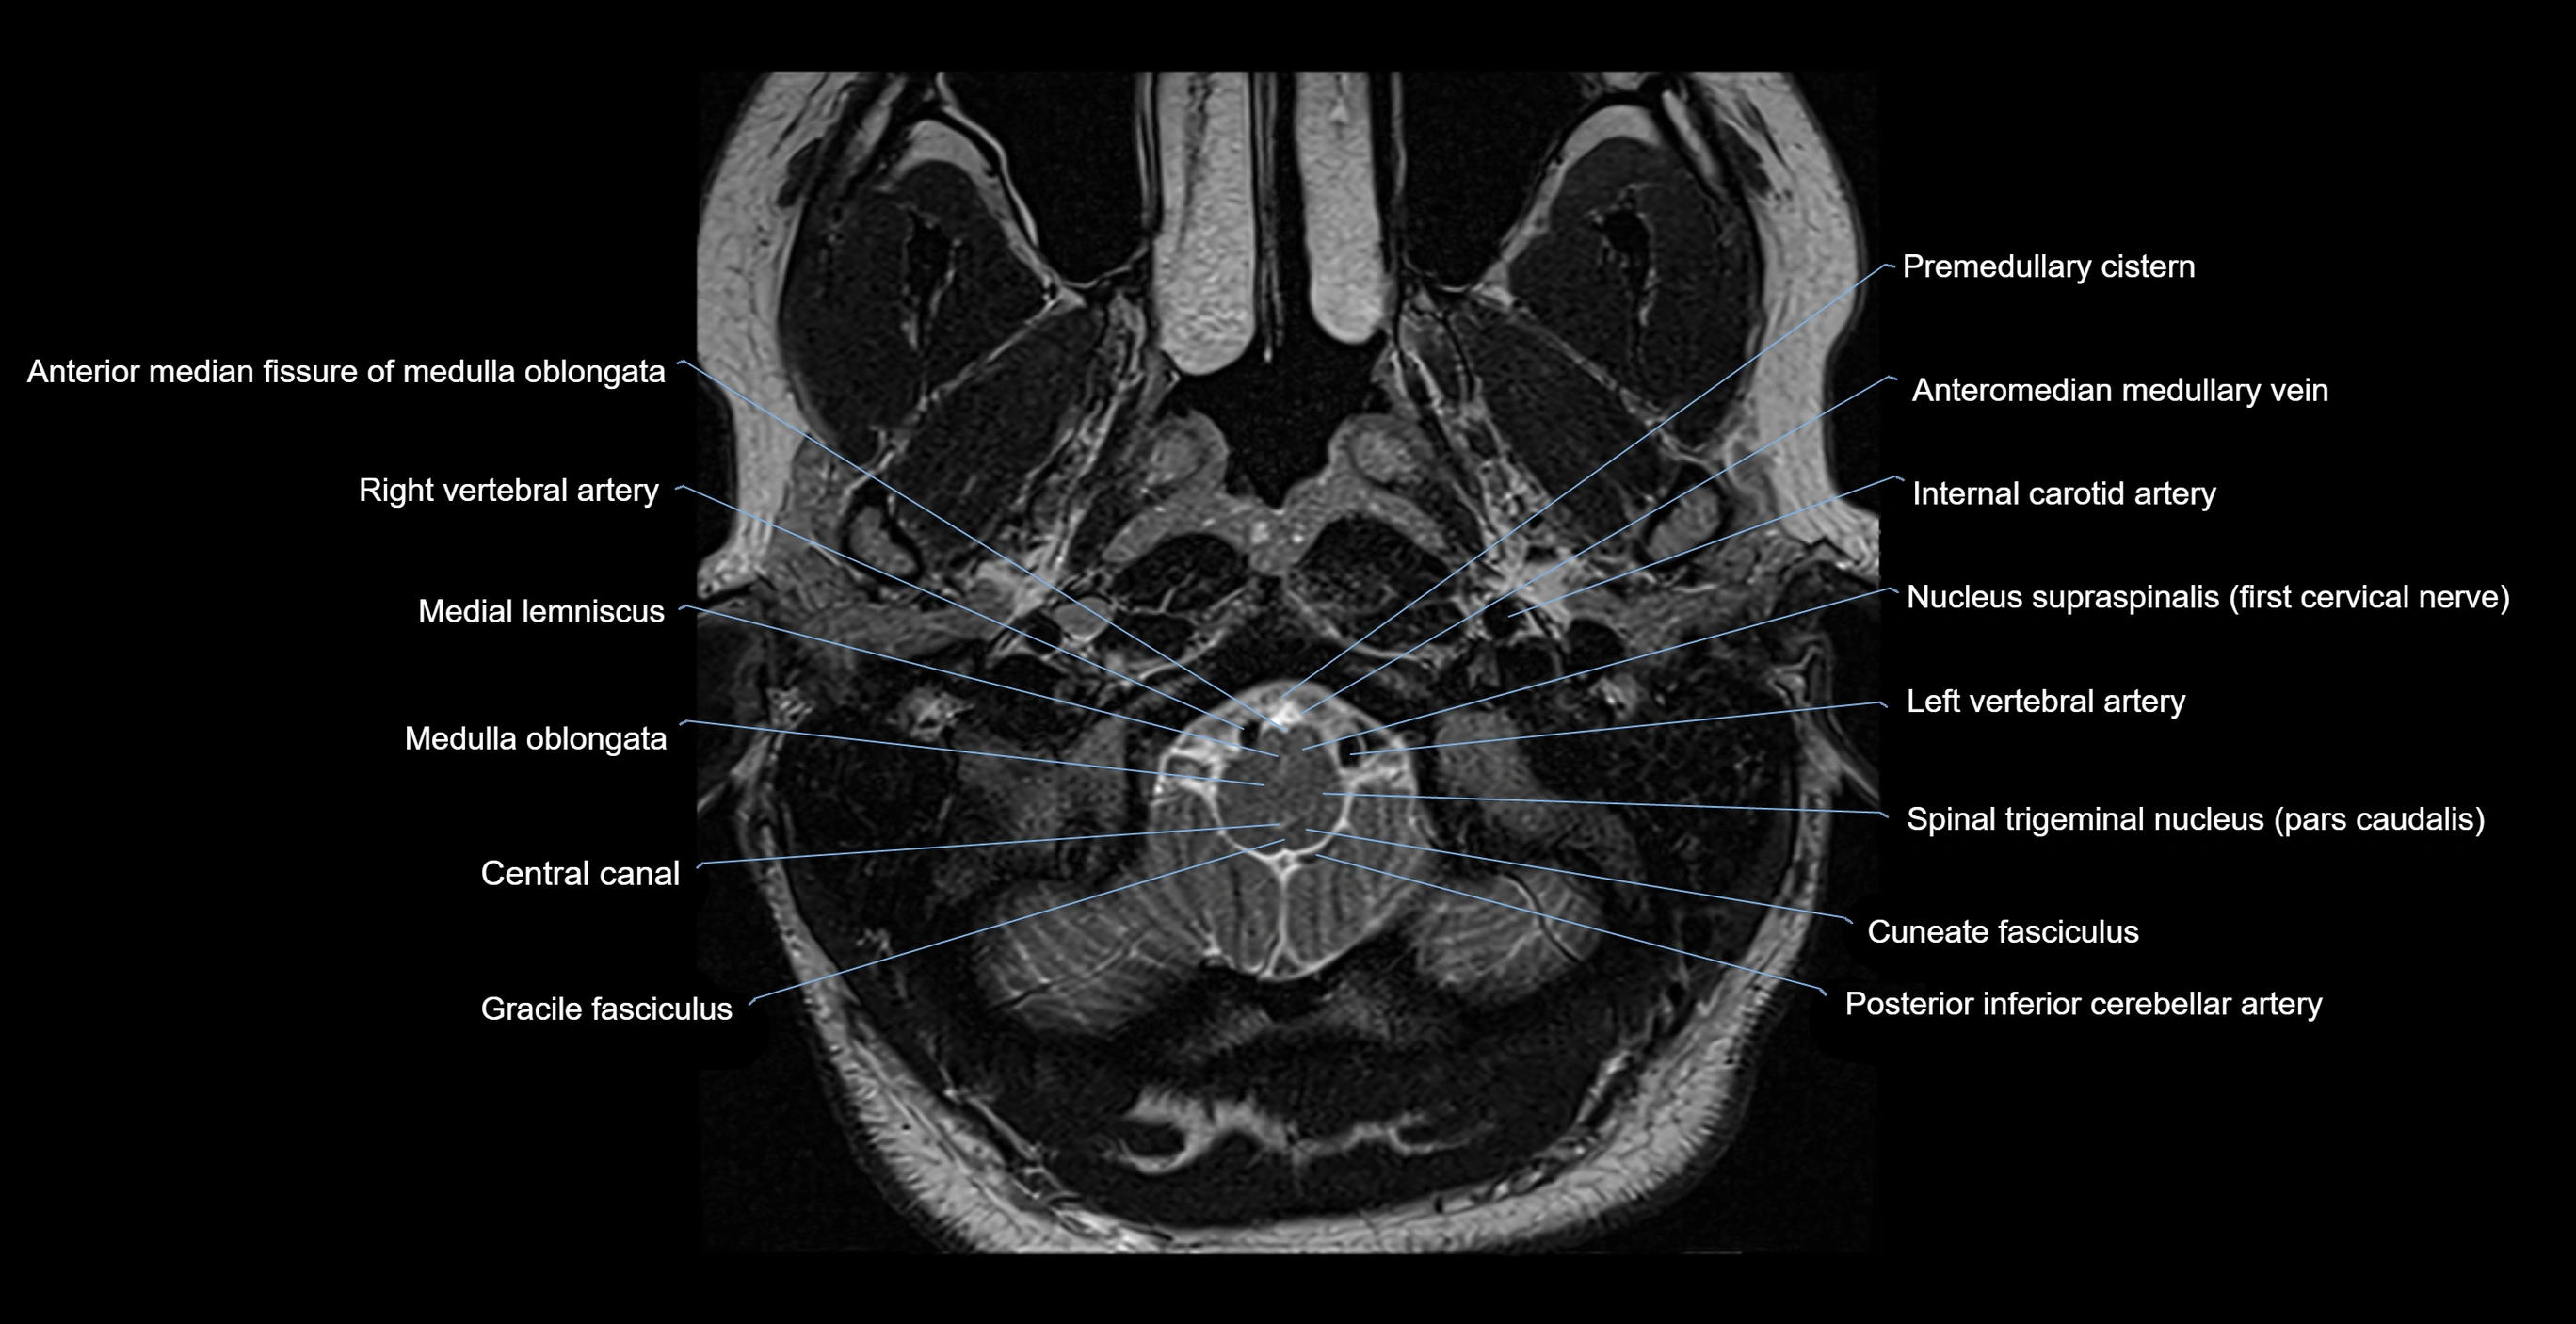

MRI images